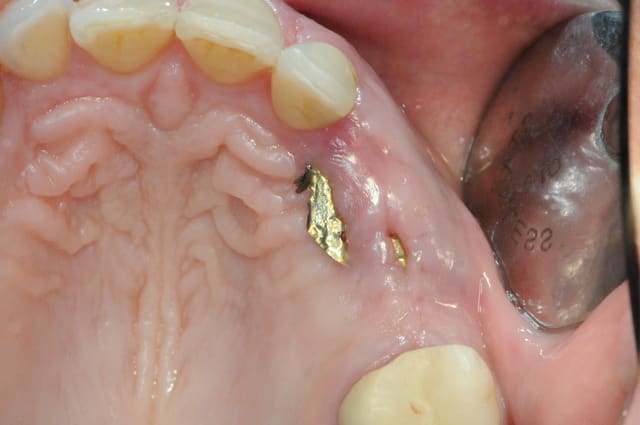

il se trouve que j'aimerais utiliser ces photos car c'est le nouveau systeme d'implants, et je n'ai encore pas d'autres cas de fracture en cours

enfin si mais pas aussi belle

j'ai donc agrandi la zone est ce qu'un pro de la photo peut faire mieux?

pour dudule, je ne fais pratiquement jamais de décharge en distal